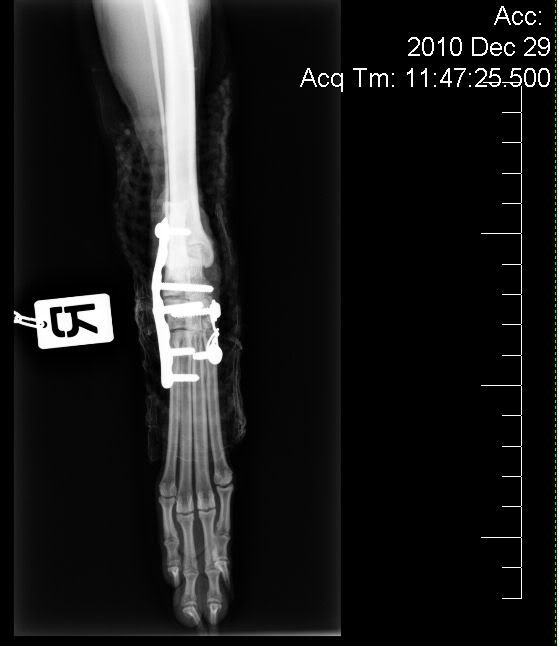

Dit is een foto van net na de 1ste operatie 27 dec-2010,

toen is het ijzerwerk er dus in gezet.Er zat toen ook gips om de poot